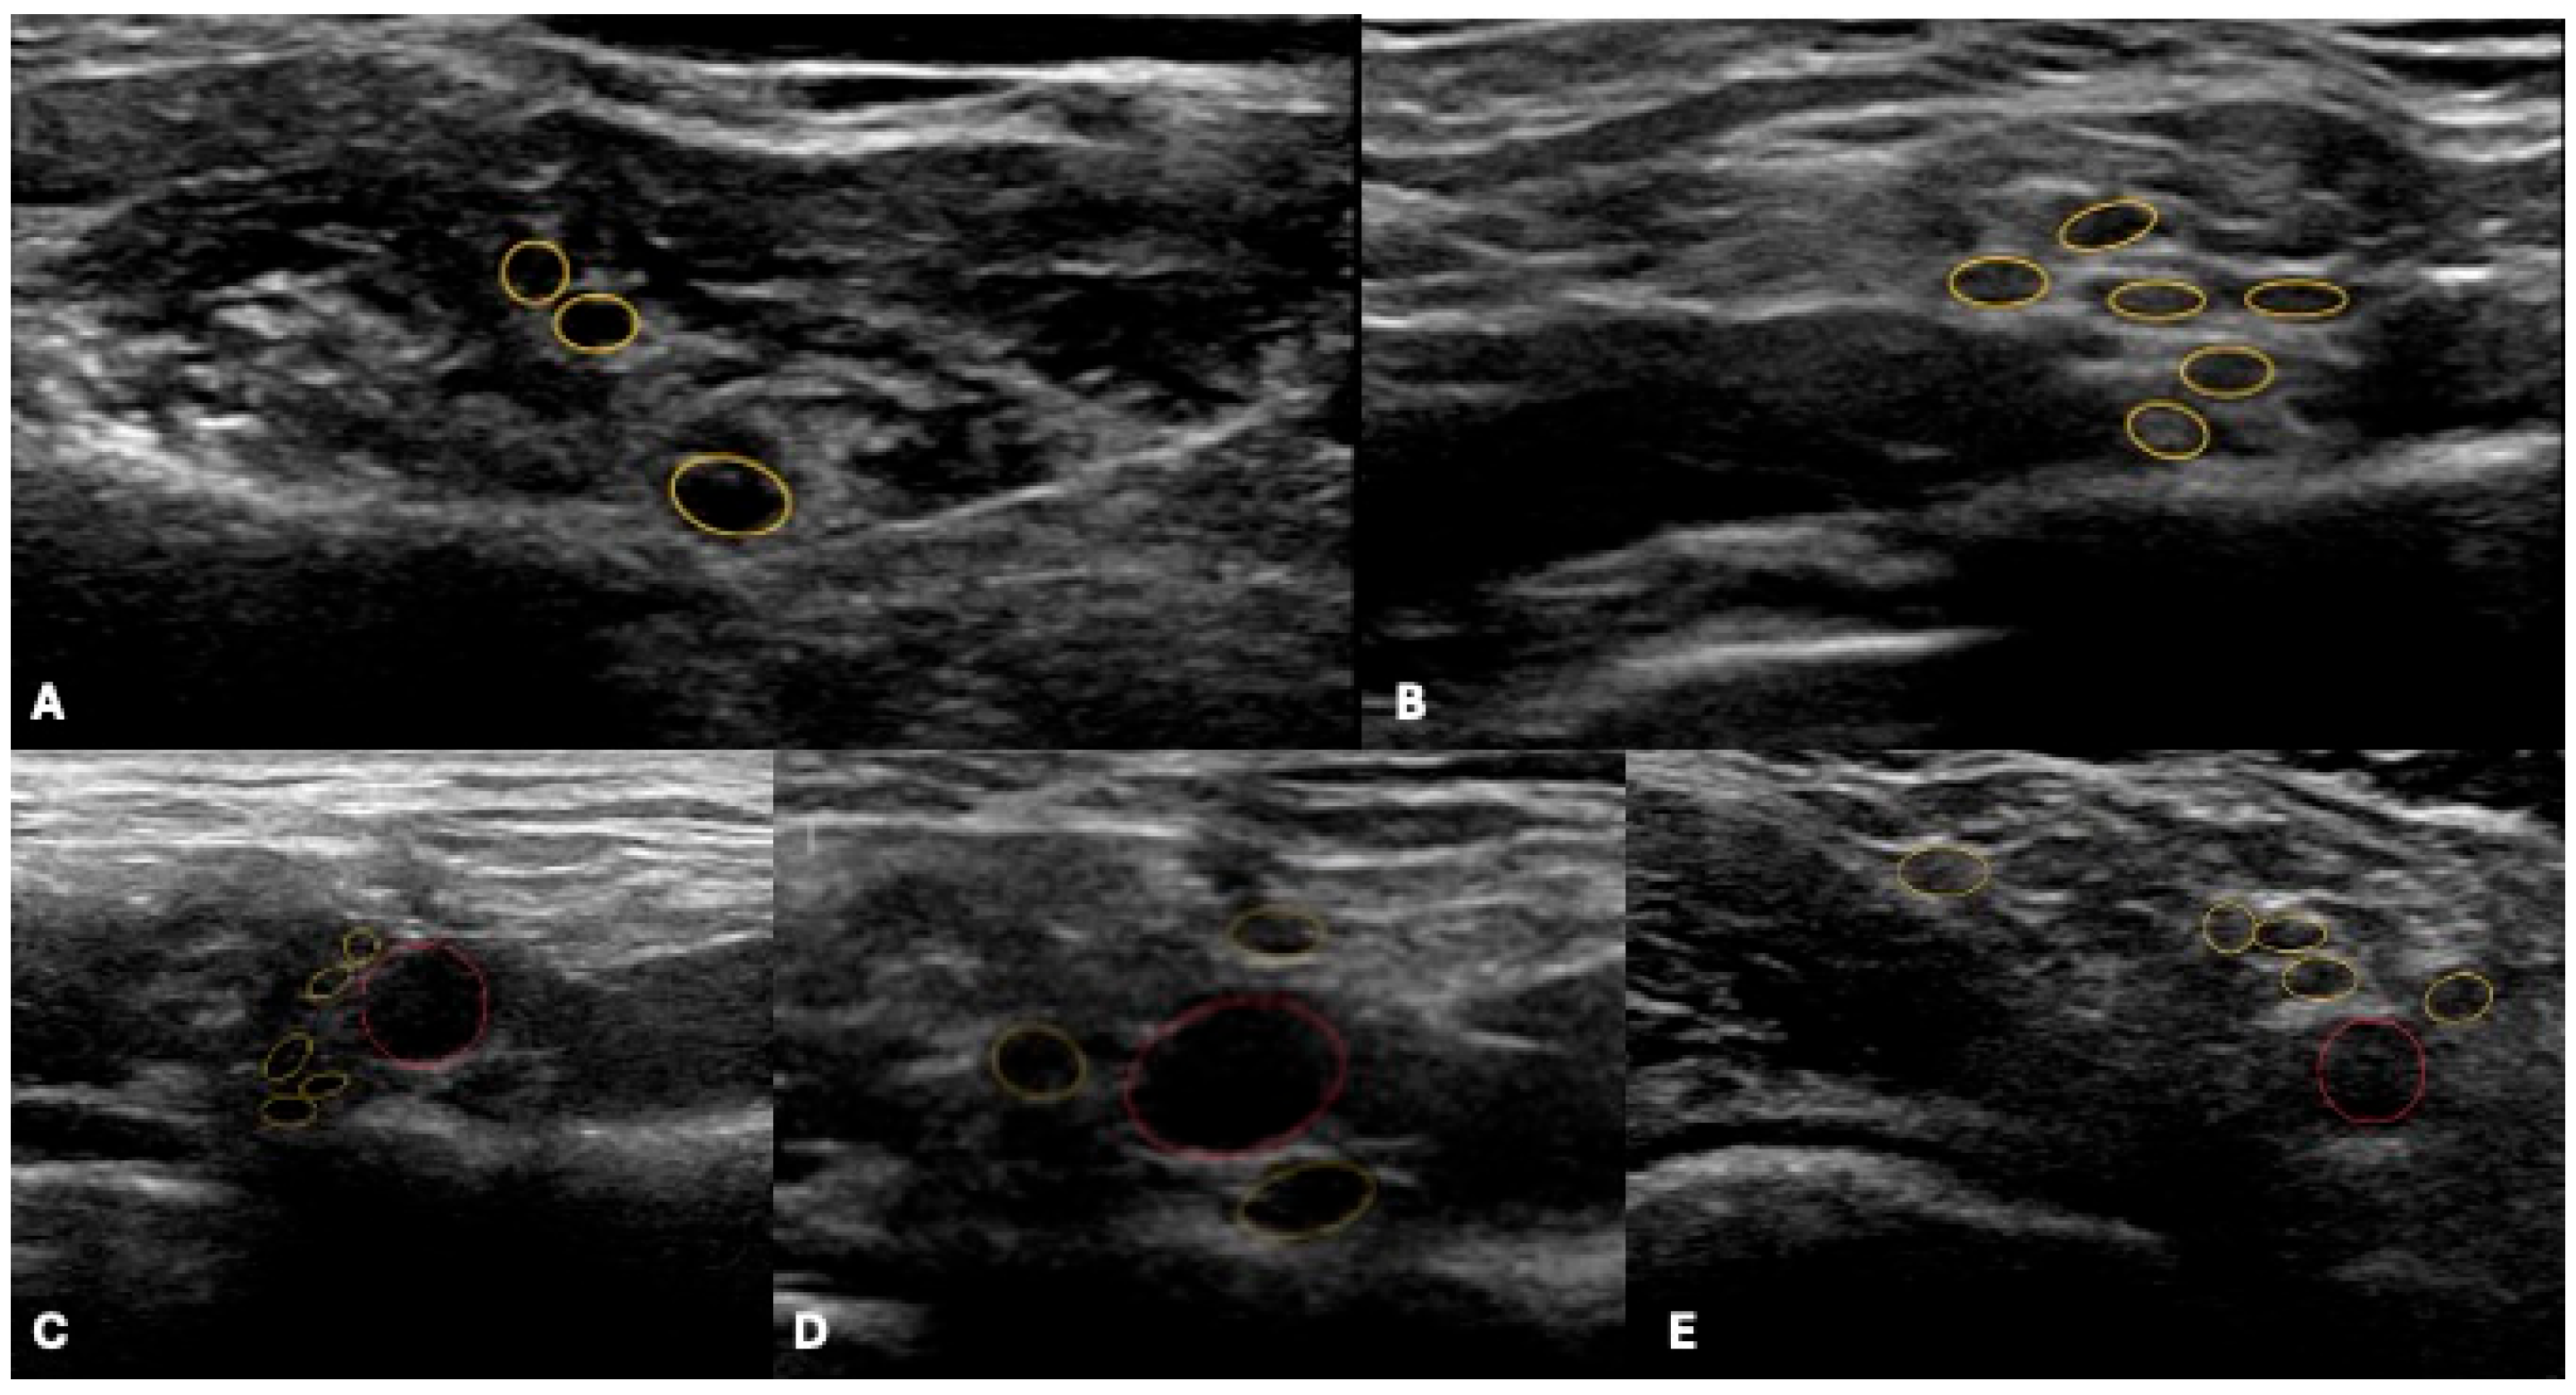

4.1. Ultrasound

- Hsu, P.-C.; Chang, K.-V.; Mezian, K.; Naňka, O.; Wu, W.-T.; Yang, Y.-C.; Meng, S.; Ricci, V.; Özçakar, L. Sonographic Pearls for Imaging the Brachial Plexus and Its Pathologies. Diagnostics 2020, 10, 324. [Google Scholar] [CrossRef]

- Zaidman, C.M.; Seelig, M.J.; Baker, J.C.; Mackinnon, S.E.; Pestronk, A. Detection of Peripheral Nerve Pathology. Neurology 2013, 80, 1634–1640. [Google Scholar] [CrossRef]

- Baute, V.; Strakowski, J.A.; Reynolds, J.W.; Karvelas, K.R.; Ehlers, P.; Brenzy, K.J.; Li, Z.J.; Cartwright, M.S. Neuromuscular Ultrasound of the Brachial Plexus: A Standardized Approach. Muscle Nerve 2018, 58, 618–624. [Google Scholar] [CrossRef]

- Griffith, J.F. Ultrasound of the Brachial Plexus. Semin. Musculoskelet. Radiol. 2018, 22, 323–333. [Google Scholar] [CrossRef]

| Benign PNST | Well-defined, hypoechoic mass, posterior enhancement, preserved nerve continuity | T1 iso, T2 hyper with target sign, intense enhancement | Target and tail signs | No invasion, mobile, ‘split-fat sign’ |

| MPNST | Ill-defined, irregular, possible invasion | Heterogeneous T2, large, infiltrative | Nerve-effacing sign, no target | NF1, post-radiation, rapid growth |

| Metastasis | Discrete, hypervascular, lower trunks | T1 hypo, T2 hyper, enhances | Asymmetric, intense enhancement | Coexisting nodal disease |

| Neuralgic Amyotrophy (PTS) | Suprascapular nerve CSA > 4.2 mm2, fascicular disorganization, hourglass constriction | Hourglass constrictions, focal fascicular narrowing, muscle edema | — | CSA cutoff, dynamic fascicle changes |

| CIDP/MMN | Symmetric/multifocal root/median nerve enlargement, intraneural hypervascularity (SMI) | ‘Onion bulb’ pattern in hereditary forms, diffuse root enlargement | — | Hypervascularity supports inflammation |

| Thoracic Outlet Syndrome (TOS) | Lower trunk indentation/swelling, ‘wedge-sickle sign’, dynamic Doppler with provocative maneuvers | Fibrous bands, vessel impingement, dynamic compression on positional MRI | — | Provocative maneuvers key for diagnosis |